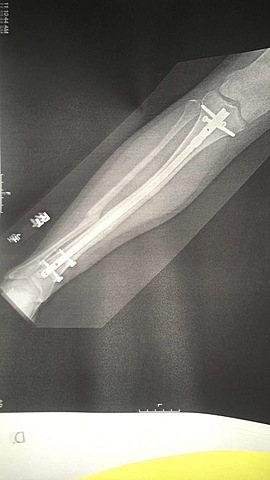

When I got surgery i was put in a splint and my leg felt very heavy because I had metal in my bones.

We went in for another check up and they said that my leg was doing really good. The x-ray stilled looked scary because my fibula was still broken. they said that it had to heal on its own.